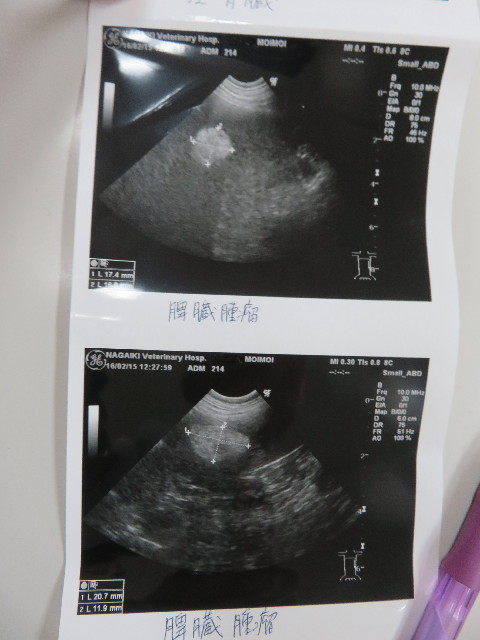

●エコー

○脾臓のマス、20.7×11.9cmと前回(前回12.7は17.5×12.2)

よりけっこう大きくなってしまっていました。

(前回はその前より小さくなっていた)

先生的には悪いものにはみえないので、これで脾臓をとる必要

があるとは思えない。とのこと。

他の検査としては鎮静剤をかけて針検という方法もありますが、

針が届くかどうかわからないそうです。

とにかく、次回のエコーは1ケ月後にして経過観察をします。